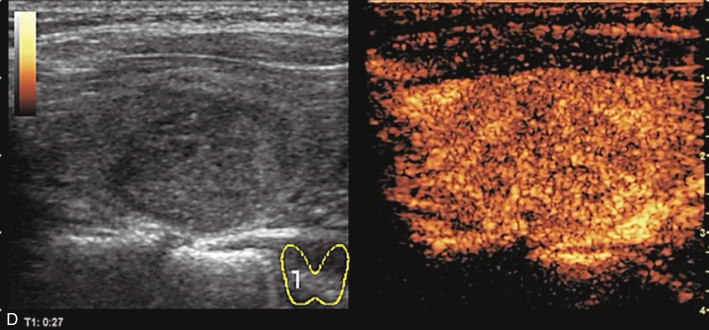

注射造影剂后,10s病灶早于周围甲状腺组织开始增强,呈不均匀高增强,13s达峰值,19s开始减退,至增强晚期病灶减退呈不均匀稍低增强。见图1-9-2、ER1-9-1。

图1-9-2 甲状腺髓样癌造影图像

A.造影后10s;B.造影后13s;C.造影后19s;D.增强晚期

甲状腺髓样癌常见超声造影表现为低增强、不均匀低增强及向心性低增强。但若病灶内血管分化较多,也可能出现高增强表现。